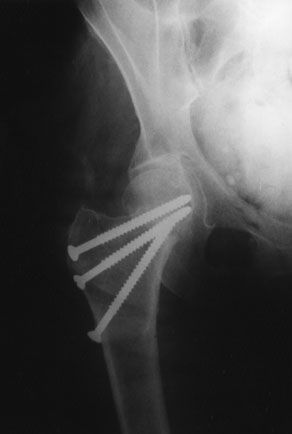

Mise au point Fractures de l'extrémité supérieure du fémur en coxa valga et tamponnade : mythe ou réalité ? , Louis Pidhorz CHU d'Angers, 4 Rue Larrey, 49033 Angers, France N°110 - Janvier 2002 ● 11 min de lecture